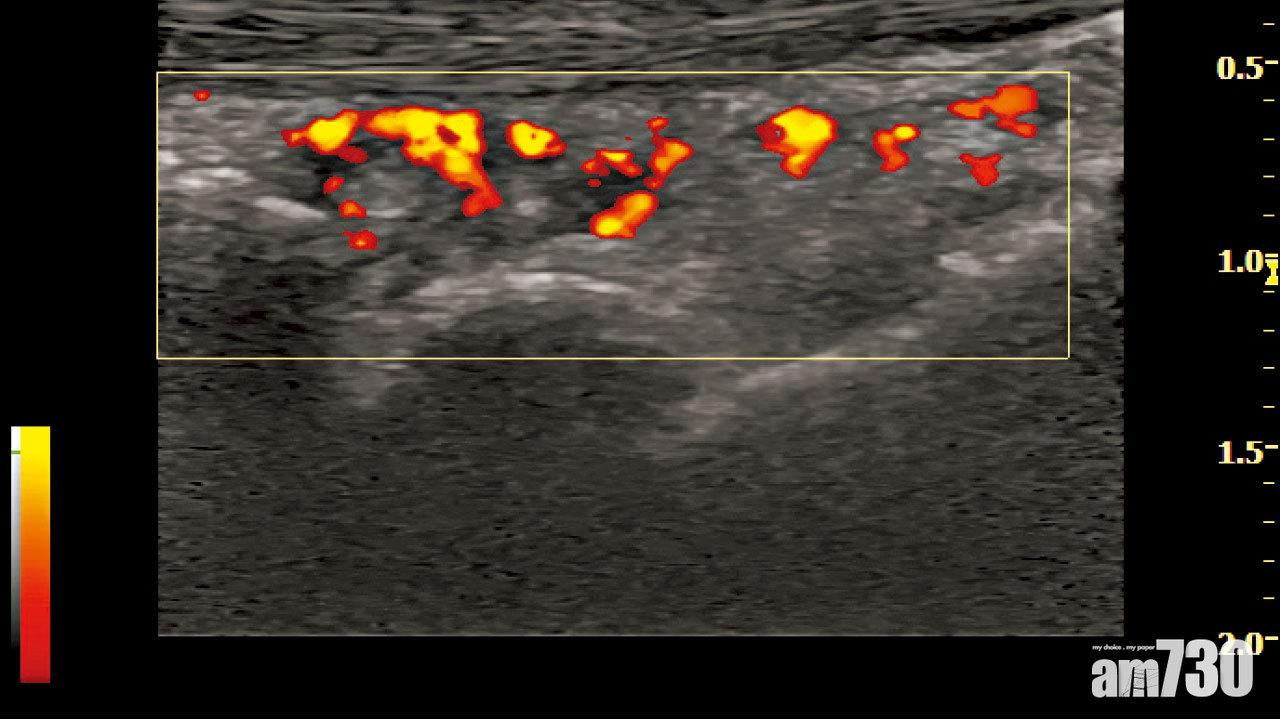

此技術讓風濕科醫生能清楚看見關節和軟組織的結構和情況,相對傳統的觸診檢查更準確和客觀。以關節痛為例,痛楚可以由關節退化或發炎性關節炎所導致,例如類風濕性關節炎。如臨床上有懷疑,醫生可透過超聲波掃描尋找發炎證據。骨膜增厚和多普納超聲所偵測的紅色訊號代表關節發炎,有可能是免疫系統失調而導致關節發炎。另一方面,如果只有骨刺而沒有紅色訊號,便是退化。